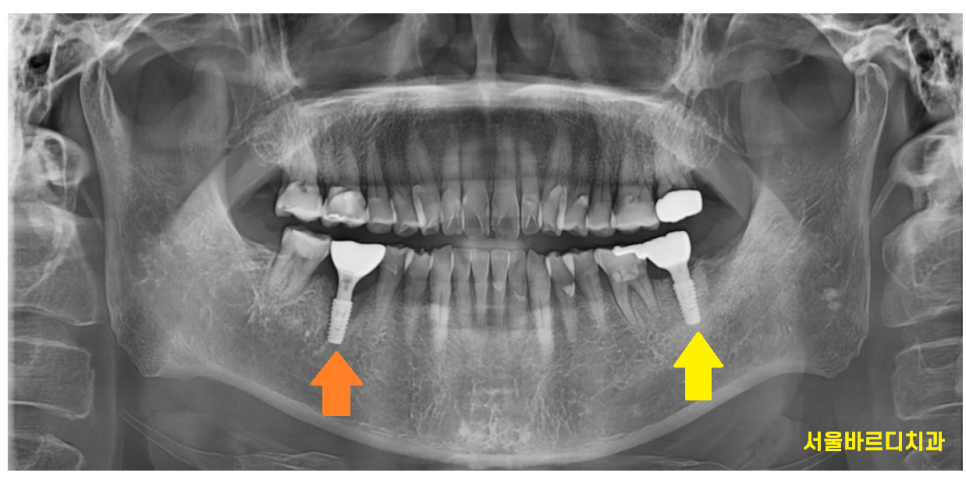

치료할 부분은 반대편에도 있었는데요

230214

아프지는 않다고 하셨지만

오른쪽 아래 어금니 치아도 염증이 있었습니다.

231029

이미 잇몸 밖으로 여드름 마냥

고름이 나오고 있었거든요ㅠㅠ

230926

치료 기간을 단축하기 위해서라면

중간에 수술을 하였어도 되었지만습니다.

임플란트 치료 경험이 없으셨기에

한쪽 우선 끝내놓고

임플란트 치료의 전 과정을 겪어보게 한 후

반대편 수술을 진행하였습니다.

240329